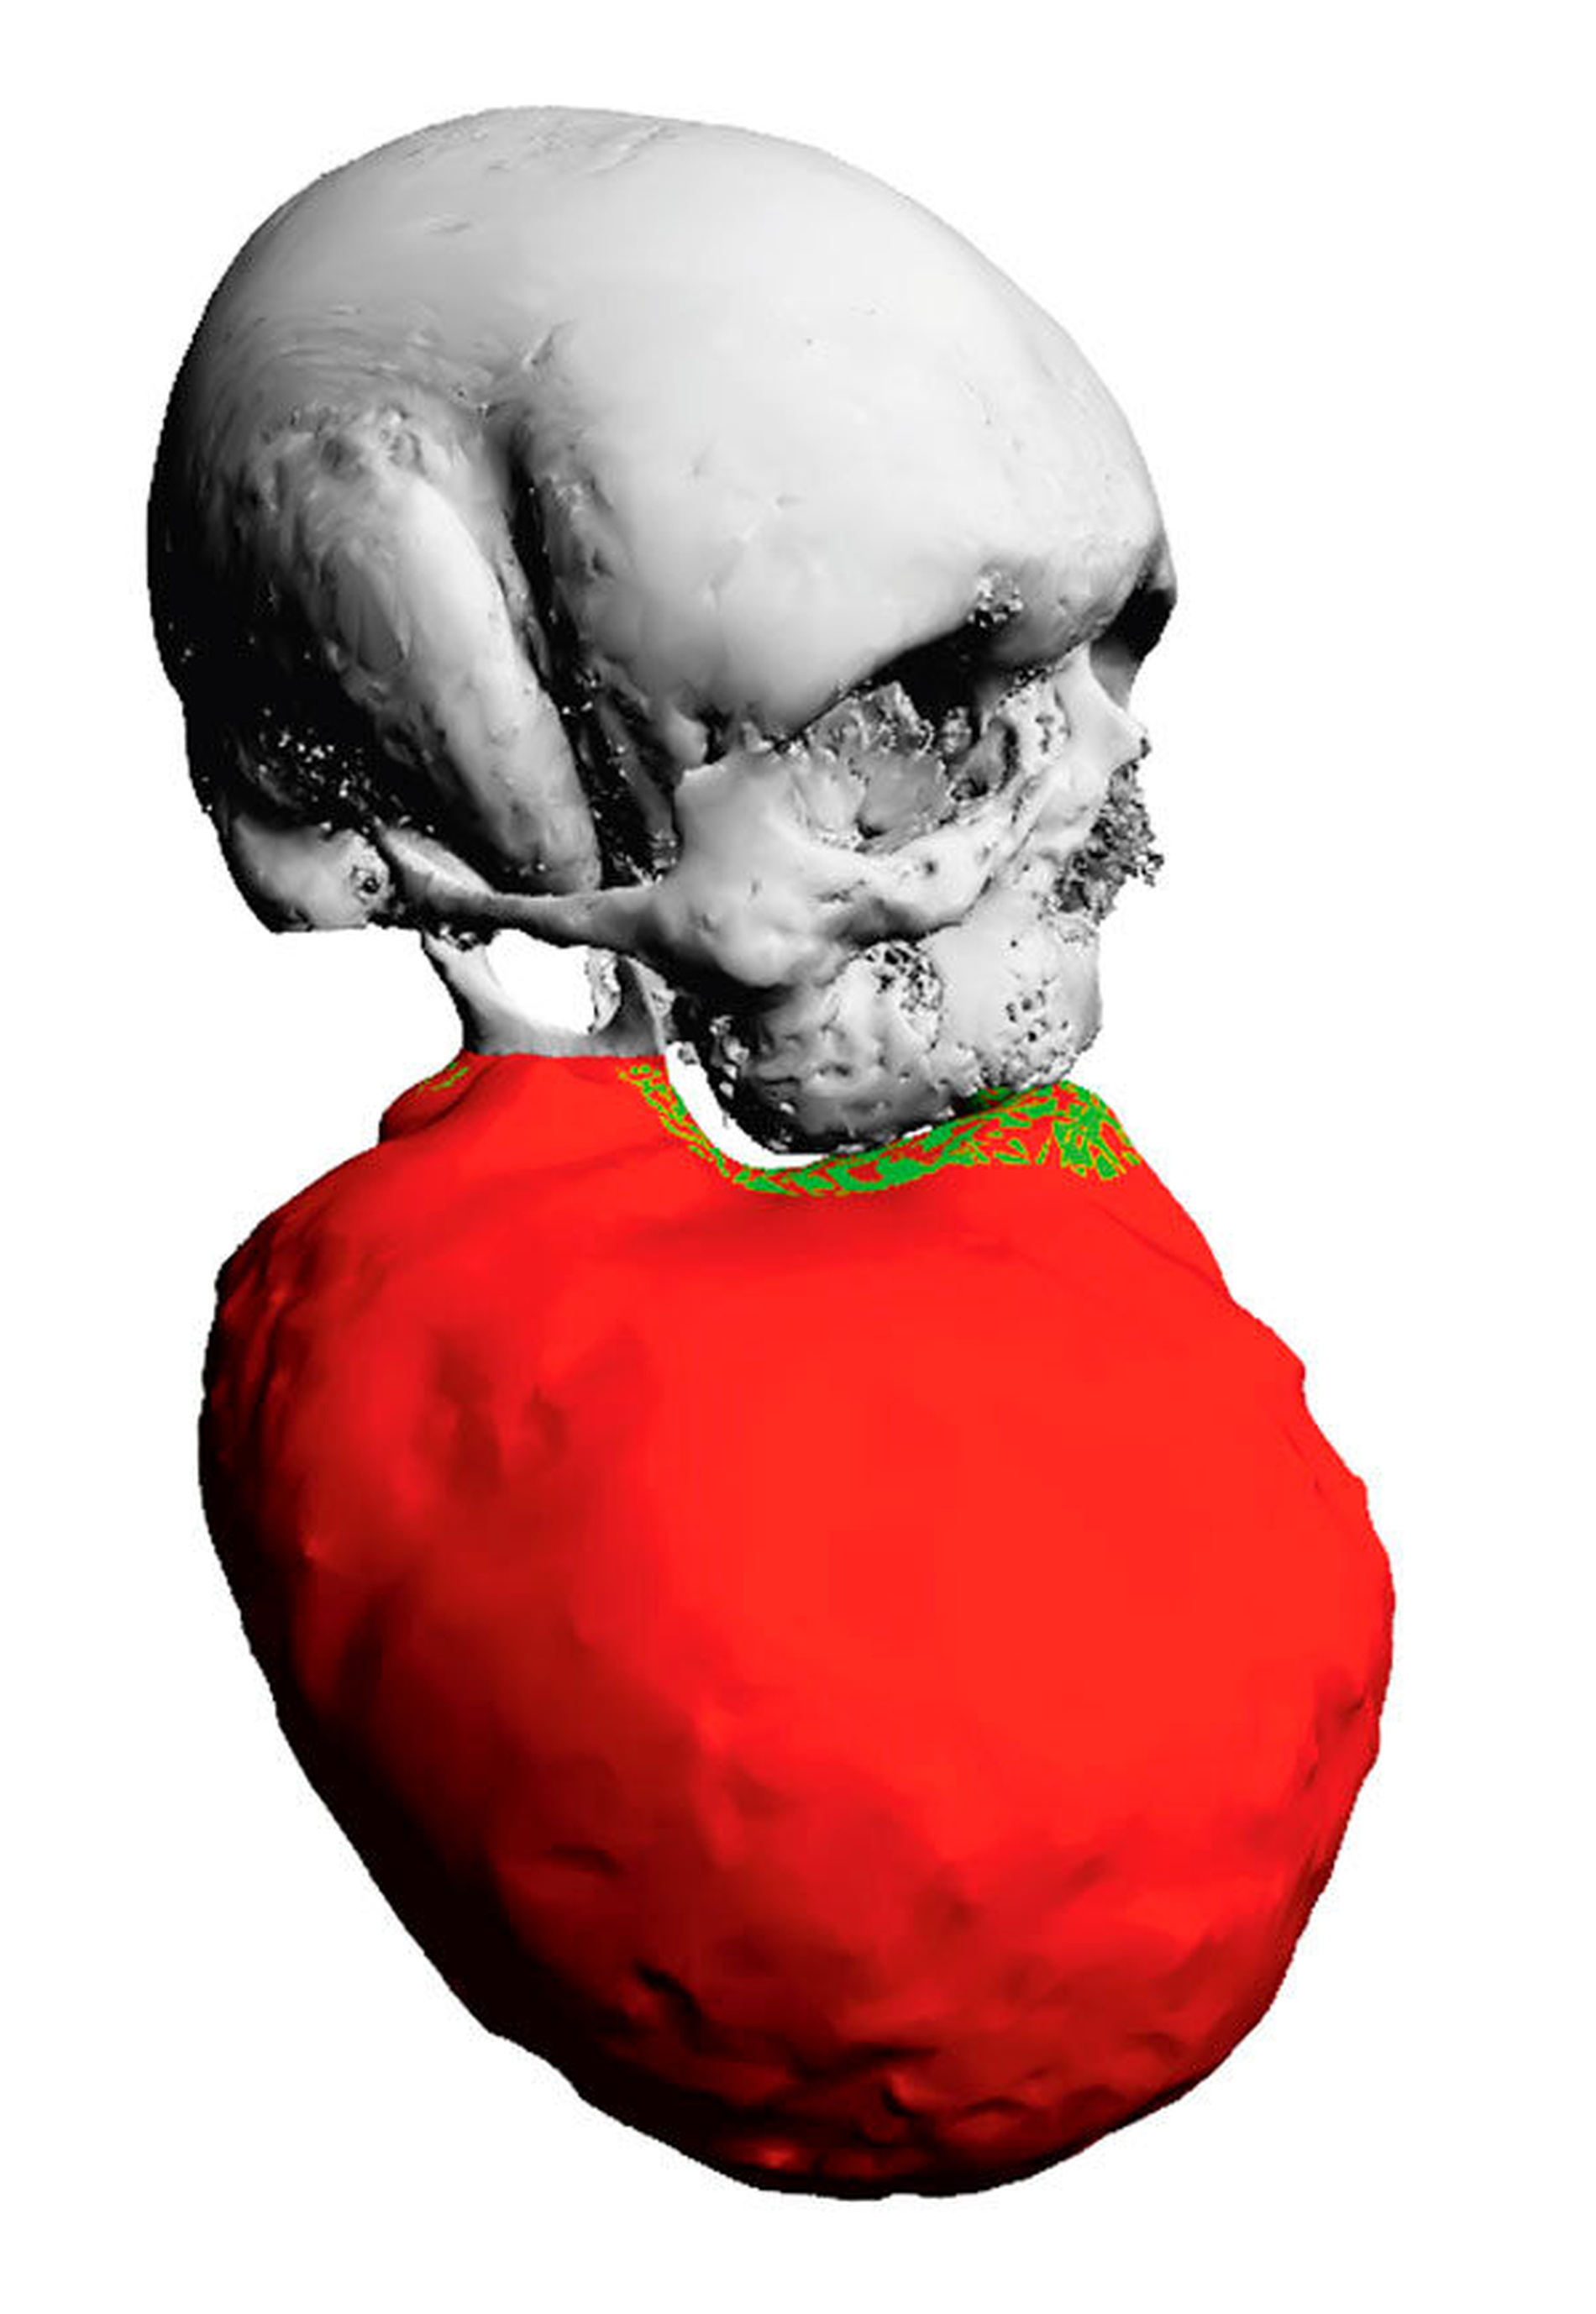

Klinisch zeigte sich eine circa 30 cm x 28 cm x 15 cm große, knochenharte und den Unterkiefer zu drei Vierteln umgreifende Raumforderung ohne Vincent-Symptomatik (Abbildung 1). In der Computertomografie zeigte sich eine inhomogene, blasige und hypodense Raumforderung mit Milchglasanteilen (Abbildung 2). Geplant wurde eine Abtragung der Veränderung mit Rekonturierung des Unterkiefers unter Verwendung eines statistischen 3-D-Formmodells, mit dessen Hilfe die ursprüngliche Form des Unterkiefers ermittelt wurde (Abbildung 3a). Im CAD/CAM-Verfahren wurden vier Resektionsschablonen hergestellt, um die geplante Osteotomie intraoperativ umzusetzen (Abbildung 3b).